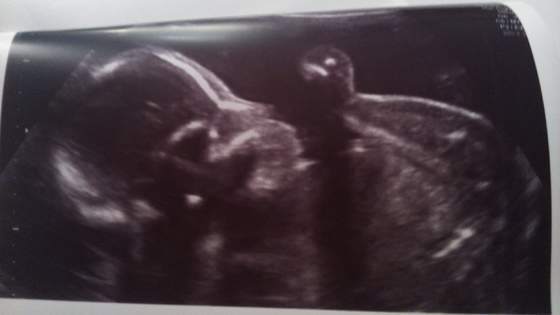

ja też po wizycie jestem

wszystko w normie, jedynie wielka rośnie

pani doktor powiedziała "ale ma fajny tłuściutki brzuszek"

no ale najważniejsze że wszystko ok

a to nasza maleńka